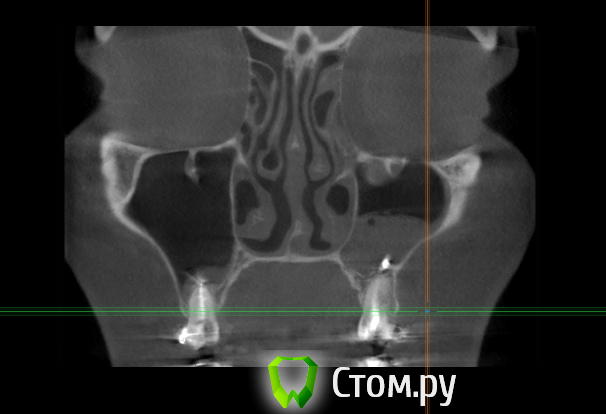

enka Опубликовано 17 апреля, 2014 Поделиться Опубликовано 17 апреля, 2014 Уважаемые доктора, была проблема внчс, теперь после контрольного ОПТГ нашлись еще проблемки! Поясните пожалуйста, что с ними делать? На данный момент ничего не беспокоит (выделений из носа нет, зубы не болят). Спасибо! Ссылка на комментарий

Bier Опубликовано 17 апреля, 2014 Поделиться Опубликовано 17 апреля, 2014 материал в пазухе, надо убирать. Качество пломбировки зубов по этим срезам не понять. Ссылка на комментарий